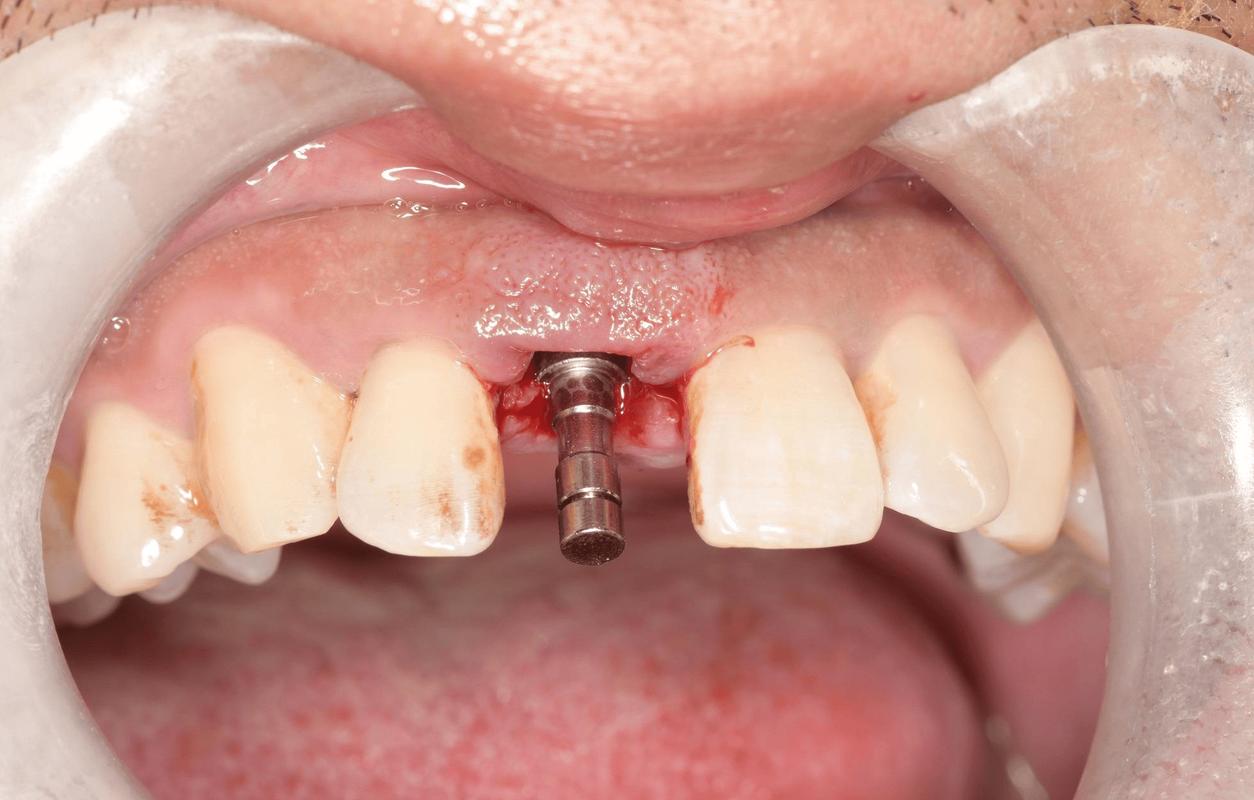

(图片来源网络,侵删)